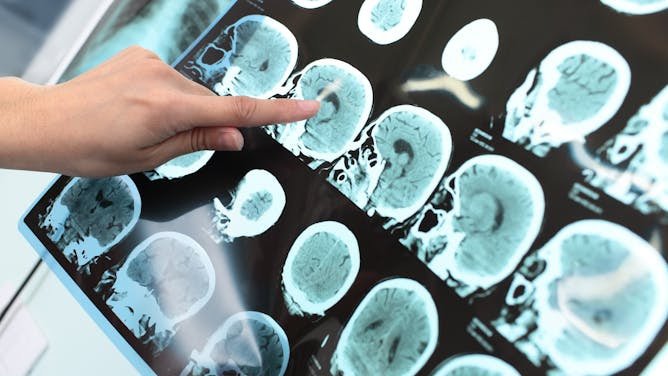

CrónicasCarga persistenteDiabetes, hipertensión, cáncer y enfermedad cardiovascular concentran alta demanda.

InvestigaciónVacunas e IAEnsayos, vigilancia genómica y salud digital avanzan como herramientas estratégicas.